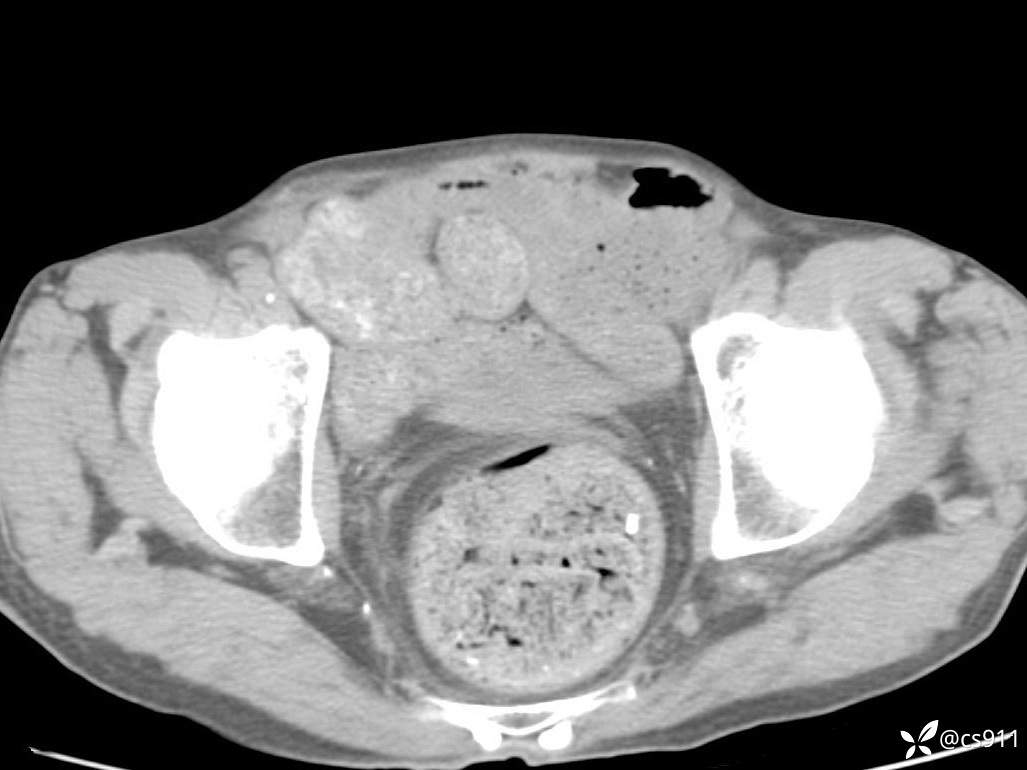

急腹症之急诊CT,原因?答案公布

男,77岁,腹痛、腹胀伴恶心呕吐1天。呕吐胃内容物,非喷射性呕吐,有咖啡色样胃内容物,诉有胃穿孔病史。查体:全腹平,下腹部压痛,全腹无反跳痛,叩诊呈浊音,移动性浊音阴性,肠鸣音减弱,1-2次/分。肛检:直肠未扪及明显肿物,可触及大量粪块。

T 36.6℃ P 80次/分 R 26次/分 BP 100/60mmHg

白细胞(WBC) H 14.55 10e9/L 4-10

红细胞(RBC) 4.58 10e12/L 4.3-5.8

中性粒细胞百分率(NEUT%) H 85.7 % 40-75

血淀粉酶(AMY) HH 1859 U/L 35-135

癌胚抗原(CEA) H 27.44 ng/ml 0-5

呕吐物 潜血试验 * 阳性 阴性

患者轮椅入室检查神志清楚, 能配合摆位和呼吸